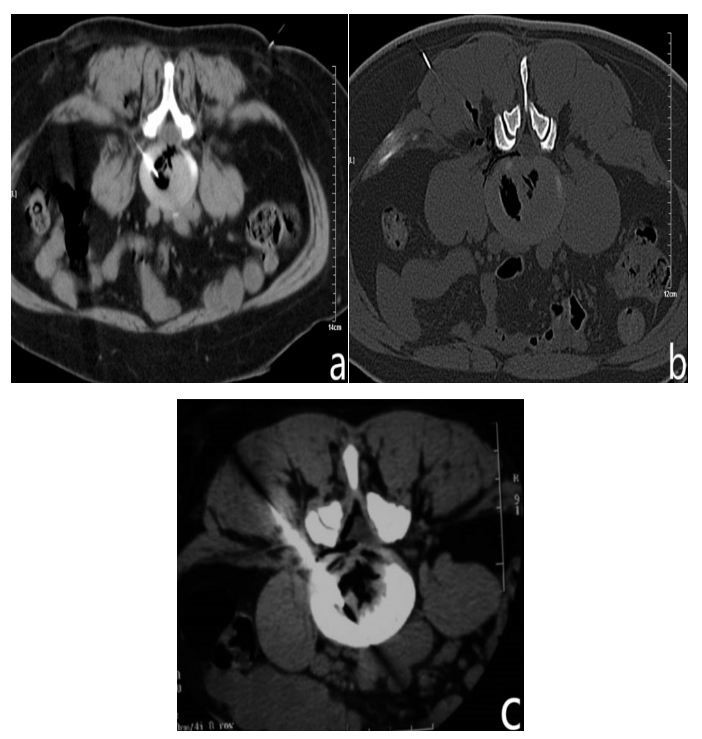

In this group ,181 patients were followed up, the incidence of ozone-replicating pain was 89.7% in 243 intervertebral discs for effective treatment. The incidence of ozone-replicating pain was 45.2% in 62 discs for Ineffective treatment (Table 1). In comparison, the former is significantly higher than the latter. Table 2 shows, the intervertebral disc is divided into three types according to ozone CTD lesion :1. internal fissure type (Figure a): the inner layer tear of the fibrous ring is not more than 1/3, C T D visible ozone diffusion does not exceed 1/3 within the fiber ring. 2. Tear type (Figure b): The fibrous ring is torn to a third of the outer layer, C T D ozone escapes to the trailing edge of the fiber ring; 3. Rupture type (Figure c): rupture of outer ring of fiber, C T D ozone leaks into the epidural space.Of those who are effective, the percentage of fracture, tear and internal fissure is 50%,38% and 12% respectively. Of those who are ineffective, the percentage of fracture, tear and internal fissure is 38%,29% and 33% respectively.In 168 disc,the positive rates of reproduction pain caused by classical discography and ozone discography were 25% and 57% respectively. The latter is significantly higher than the former in comparison of 2 groups (Table 3).

Figure a-c: (a) Image of intervertebral disc inner rupture in ozone contrast; (b) Image of strata externum disc tear in ozone contrast; (c) Image of intervertebral disc rupture in ozone contrast.